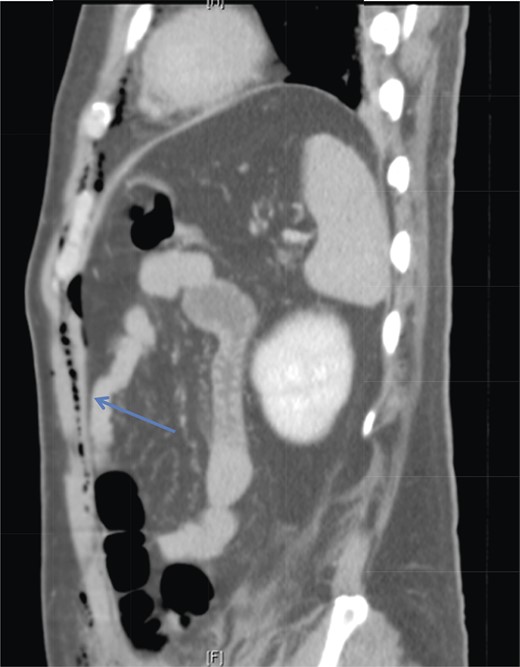

A 42-year-old male with a past medical history of hypertension was admitted for an elective TEP repair of his left inguinal hernia. Endotracheal intubation and general anesthesia were given uneventfully. The extraperitoneal space was developed with a balloon space maker, and insufflation of carbon dioxide at a maximum pressure of 12 mmHg was performed. Intraoperatively, a large incarcerated indirect left inguinal hernia containing omentum was reduced. A Optilene mesh (10 × 12 cm) was placed and tacked appropriately after hernia reduction. There were no obvious tears in the peritoneum and the total operative time was ∼90 min. No elevation of end-tidal CO2 was noted during the surgery and the patient was extubated successfully. The patient subsequently complained of left-sided chest pain on the same night of the surgery. He did not have abdominal pain. He had subcutaneous crepitus extending from the left groin to the left chest. His cardiac enzymes were negative and his electrocardiography revealed a sinus rhythm with no acute ischemic changes. A plain radiograph of the chest showed a sliver of lucency in the mediastinum suspicious for pneumomediastinum, with no obvious pneumoperitoneum or pneumothorax seen (Fig. 1). Computed tomographic (CT) imaging of the thorax and abdomen confirmed the radiograph finding of pneumomediastinum and diffuse subcutaneous emphysema tracking along the abdominal muscles bilaterally, as well as a small amount of free air and stranding in the left posterior pararenal space (Figs 2–4). The patient was treated conservatively with oral analgesia and supplemental oxygen. His chest pain resolved by the third postoperative day and he was discharged well. He was advised to avoid air travel for 1 month. He was reviewed in clinic at the 1-week and 1-month intervals and did not report any further chest pain or respiratory symptoms. His operation site healed well and he remained recurrence free.

Sagittal section of CT abdomen demonstrates air tracking along the anterior extraperitoneal space (arrowhead) into the anterior mediastinum and preperitoneal fat.

Laparoscopic CO2 can enter the retroperitoneal space and track along tissue planes into the pleural space and mediastinum [4]. Chien and Soifer [7] reported a case of pharyngeal emphysema complicating a laparoscopic hernia repair, and postulated that myopectineal dissection may lead to CO2 tracking retroperitoneally into the thorax. This is a possible cause of pneumomediastinum in our patient, as his CT imaging showed the presence of left posterior pararenal stranding, supporting a possible retroperitoneal dissection of CO2 to the thoracic cavity. Another pathway for transdiaphragmatic extension of air into the mediastinal space was proposed by Meyers [8]. The endothoracic fascia is continuous with the extraperitoneal space of the fascia transversalis. Extraperitoneal gas can dissect through the anterior gaps of the diaphragm between the sternal, xiphoid and costal origins of the diaphragm. With the aid of anatomical studies in cadavers, Kleinman et al. confirmed these observations [6]. This potential pathway likely explains the entry of CO2 from our patient's abdominal wall (extraperitoneal space) into the mediastinum, without the presence of pneumoperitoneum.